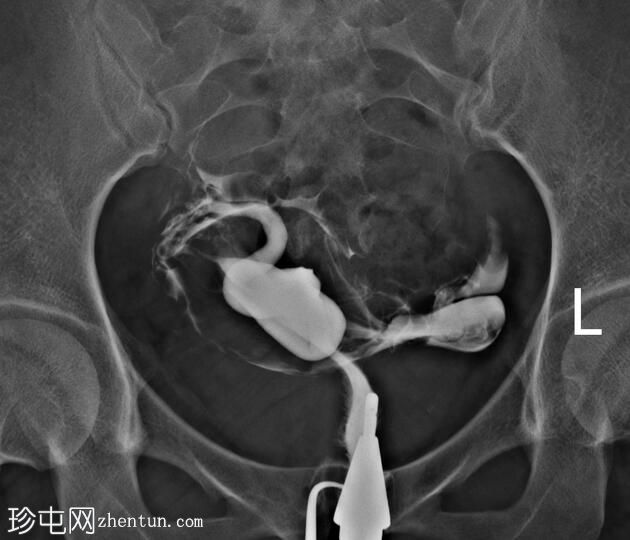

子宫体位于盆腔右侧旁中线,形态及轮廓正常。

宫颈管长度及黏膜表面正常,扩张正常。

右侧输卵管充盈,呈逐渐扩张,内有造影剂残留,无因输卵管积水导致的造影剂溢出。

左侧输卵管出现腹膜溢出。

输卵管积水是指输卵管内充满液体的扩张。